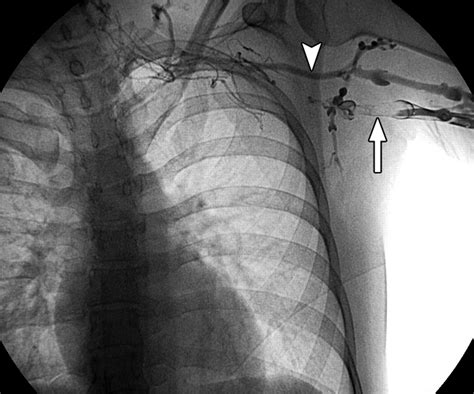

Venography Involves injecting a contrast dye into the veins and taking X-rays to visualize the blood flow and identify blockages.